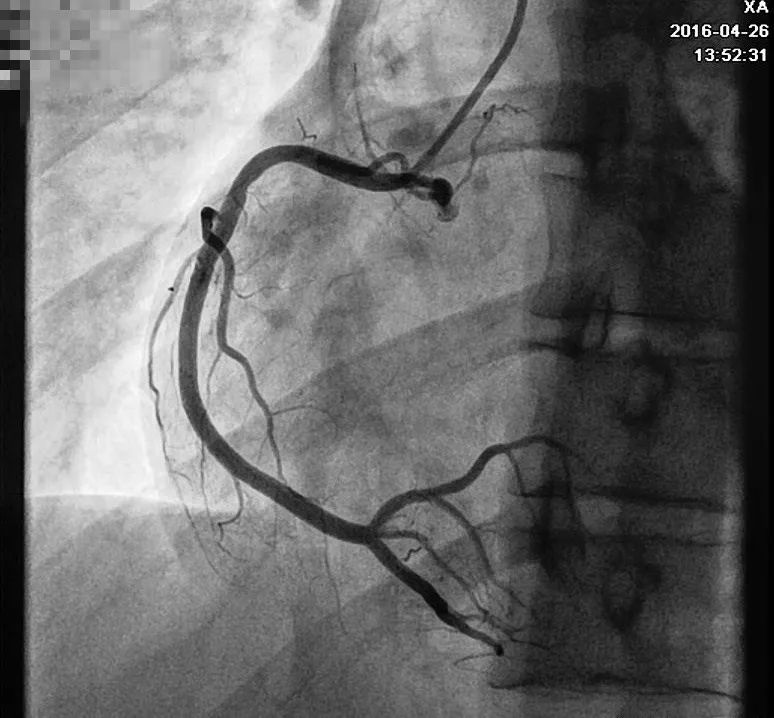

回顾患者病例特点:青年男性,有典型心绞痛发作病史,心电图有特征性改变及演变(胸痛发作时心电图正常;胸痛缓解时,V2~V5导联T波倒置),考虑Wellens综合征。行冠状动脉造影检查示左前降支(LAD)近中段80%~90%弥漫性狭窄,血流慢(图6),右冠近段狭窄20%~30%,回旋支开口狭窄20%~30%(图7)。于LAD置入2枚支架,复查造影提示支架置入处无残余狭窄(图8)。术后规律服用上述药物治疗,未再发作心绞痛。

图7